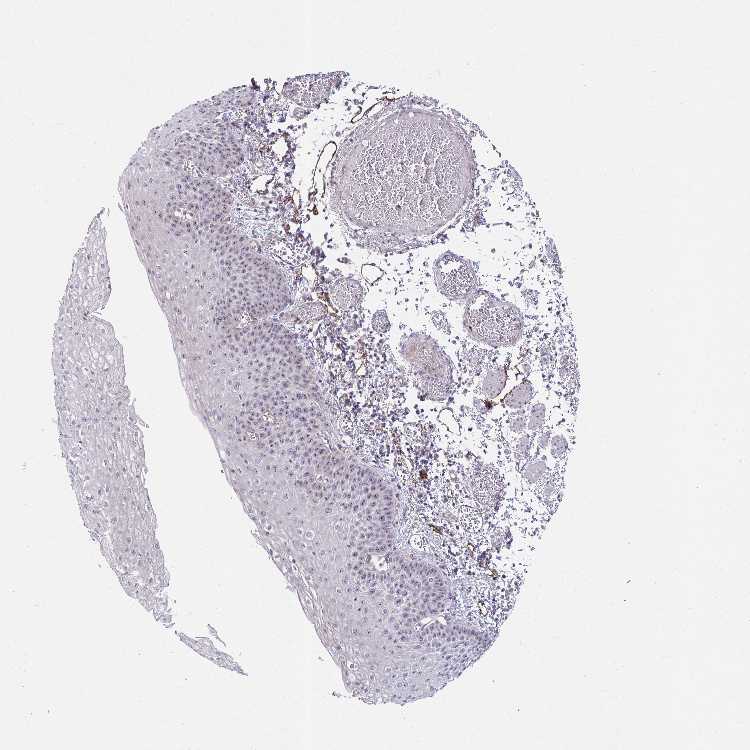

ESOPHAGUS - Antibody stainingi

Antibody staining in the annotated cell types in the current human tissue is reported as not detected, low, medium, or high, based on conventional immunohistochemistry profiling in selected tissues. This score is based on the combination of the staining intensity and fraction of stained cells.

Each image is clickable and will lead to virtual microscopy that enables deeper exploration of all samples and also displays staining intensity scores, fraction scores and subcellular localization as well as patient and tissue information for each sample.

Antibody HPA059530

Squamous epithelial cells Medium